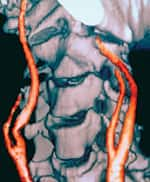

Sesame Lignans Improve Lipid ProfilesSesame lignans have been shown to improve lipid profiles in both humans and experimental animals. Unfavorable lipid profiles are a significant risk factor for cardiovascular disease. In one study, re-searchers examined the effects of sesamin on cholesterol metabolism in rats. Their study found that animals fed sesamin (0.5% of their daily diet) for four weeks had significant reductions in serum and liver cholesterol levels, irrespective of the presence or absence of cholesterol in their diet.23 The researchers also noted a significant reduction in liver activity of 3-hydroxy-3-methylglutaryl coenzyme A reductase (HMG-CoA), the rate-limiting enzyme required for cholesterol biosynthesis. According to the study authors, “since sesamin lowered both serum and liver cholesterol levels by inhibiting absorption and synthesis of cholesterol simultaneously, it deserves further study as a possible hypocholesterolemic agent of natural origin.”23 A study in rabbits showed that sesame helped improve lipid profiles by lowering total cholesterol and triglyceride levels while increasing levels of protective high-density lipoprotein (HDL).24 In addition, sesame decreased susceptibility to oxidative stress in the rabbit study.24 When vitamin E and sesamin were added to the diets of rats, LDL and very low-density lipoprotein (VLDL) levels decreased while beneficial HDL increased significantly, favorably improving the atherogenic index.25 To determine whether sesame lignans affect cholesterol levels in human subjects, Japanese re-searchers recruited 12 male patients diagnosed with hyper-cholesterolemia (high cholesterol). One group of six patients was treated with 32 mg of sesamin per day, while the second (control) group received a placebo. After eight weeks of treatment, the sesamin-treated group was found to have lower total cholesterol, LDL, and apolipoprotein B levels. In the sesamin group, average total cholesterol levels dropped from 270 to 248 mg/dL, LDL levels fell from 187 to 156 mg/dL, and apolipoprotein B levels were reduced from 188 to 168 mg/dL, thus reducing several serious risk factors for cardiovascular disease. By contrast, in the placebo group, levels of total cholesterol, LDL, and apolipoprotein B were unchanged.26 Sesame Lignans Show Antihypertensive EffectsHypertension is a silent disease that that increases the risk of stroke, heart attack, and other serious disorders. Sesame lignans have demonstrated antihypertensive effects in animals and humans. In both normotensive and hypertensive stroke-prone rats, sesame exerts a mild antihypertensive effect.27 In high-salt diets, sesame prevented the development of hypertension and of histological renal damage such as thickening of the tunica intima and fibrinoid degeneration of the arterial wall.28-33 These findings may have implications for humans because of the high salt content in the American diet. A recent human study investigated the effects of sesame oil in hypertensive patients who were being treated with a calcium channel blocker (nifedipine). The study enrolled 396 hypertensive patients, including 215 men and 181 women, with an average age of 58. Forty patients were treated only with nifedipine, while 356 patients continued to use nifedipine while switching exclusively to sesame oil in place of other edible oils in their diet. After 60 days, the average systolic blood pressure in the sesame group was reduced from 166 mm Hg to 134 mm Hg, and the average diastolic pressure dropped from 101 mm Hg to 85 mm Hg.34